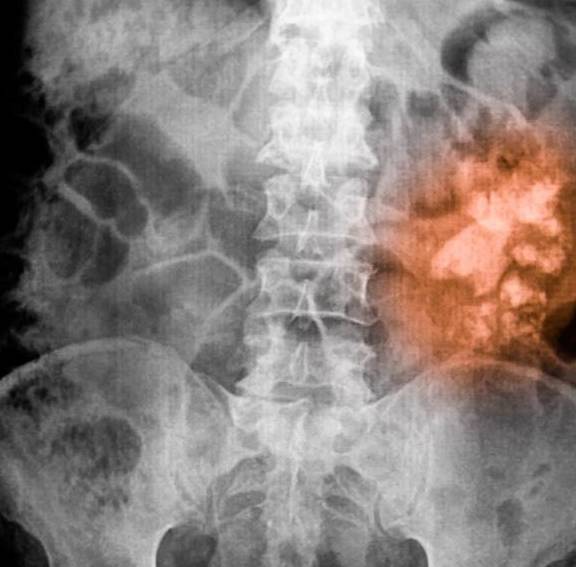

肾结石(renal calculi)是晶体物质(如钙、草酸、尿酸、胱氨酸等)在肾脏的异常聚积所致 , 为泌尿系统的常见病、多发病 , 男性发病多于女性 , 多发生于青壮年 , 左右侧的发病率无明显差异 , 90%含有钙 , 其中草酸钙结石最常见 。 40%~75%的肾结石患者有不同程度的腰痛 。

结石较大 , 移动度很小 , 表现为腰部酸胀不适 , 或在身体活动增加时有隐痛或钝痛 。 较小结石引发的绞痛 , 常骤然发生腰腹部刀割样剧烈疼痛 , 呈阵发性 。 泌尿系统任何部位均可发生结石但常始发于肾 , 肾结石形成时多位于肾盂或肾盏 , 可排入输尿管和膀胱 , 输尿管结石几乎全部来自肾脏 。 原来肾结石不是石头是晶体物质(如钙、草酸、尿酸、胱氨酸等)在肾脏的异常聚积所导致的 。

可分为肾盂结石、肾盏结石、肾实质结石 。 肾盂结石最常见 , 肾实质结石罕见 。